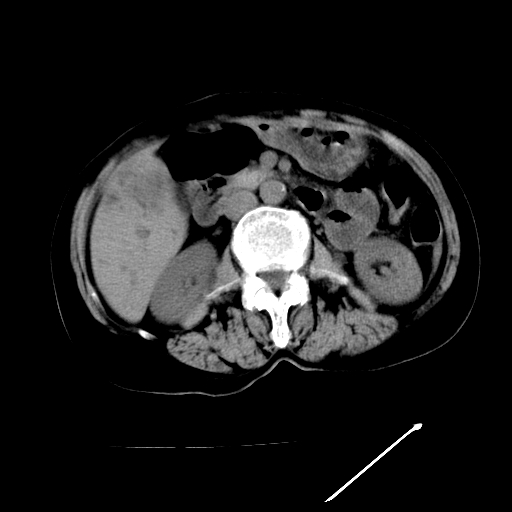

以下是引用卜一在2009-4-7 5:06:00的发言:[br]左右肝内胆管结石伴扩张合并胆系感染;不除外胆管细胞癌可能。支持! [br] [br]